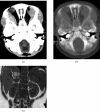

Neuroblastoma is one of the most common malignant neoplasms in childhood. The most common clinical presentation of this tumour is abdominal mass. However, affected children may have various clinical presentations as a result of disseminated metastatic disease or associated paraneoplastic syndromes at the time of diagnosis. In this article we have outlined the imaging findings in seven patients with "extra-abdominal" presentation of neuroblastoma and the pitfalls in making the correct diagnosis. The purpose of this pictorial review is to alert the general radiologist to the possible presentations of this common childhood malignancy to derive early detection and diagnosis.